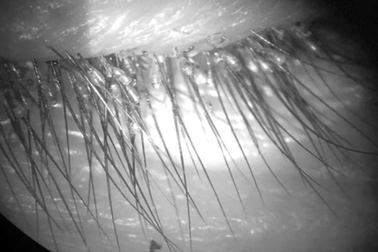

Hàng trăm con rận mu làm tổ chi chít trên mi mắt người đàn ôngThấy mắt trái ngứa lâu ngày không khỏi, ông H. đến bệnh viện khám thì phát hiện hàng trăm con rận mu trưởng thành, nhiều ấu trùng còn sống kèm vỏ kén chi chít dưới chân lông mi.

Bác sĩ tá hỏa vì hàng trăm con rận mu, trứng rận trên mi mắt bệnh nhânNam bệnh nhân đến khám vì ngứa mắt, điều trị mãi không khỏi. Bác sĩ tá hóa khi phát hiện hàng trăm ký sinh trùng và trứng ký sinh trên mi mắt bệnh nhân.